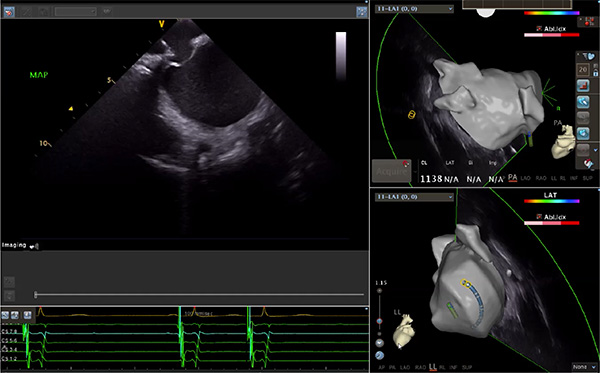

超聲心動(dòng)圖技術(shù)包括常規(guī)經(jīng)胸超聲(TTE)、經(jīng)食管超聲(TEE)、心腔內(nèi)超聲(ICE)、超聲聲學(xué)造影(MCE)、三維超聲心動(dòng)圖等,ICE是一種新興技術(shù)——將微型的換能器安裝在心導(dǎo)管的尖端,經(jīng)由外周血管輸送至心腔內(nèi)部,換能器發(fā)射聲波,對(duì)心臟及其鄰近組織進(jìn)行實(shí)時(shí)高質(zhì)量成像和(或)血流動(dòng)力學(xué)測(cè)定的超聲成像技術(shù)?;诓煌募夹g(shù)原理,心腔內(nèi)超聲導(dǎo)管被分為兩類:機(jī)械旋轉(zhuǎn)式超聲導(dǎo)管和相控陣超聲導(dǎo)管。目前,臨床上主要應(yīng)用的是相控陣超聲導(dǎo)管,ICE成像通過(guò)術(shù)者旋轉(zhuǎn)導(dǎo)管及操縱導(dǎo)管手柄上的兩個(gè)旋鈕來(lái)完成。

ICE門檻高、集成了超聲和圖像處理最前端的技術(shù),是當(dāng)前內(nèi)窺超聲方向最挑戰(zhàn)的領(lǐng)域。不同于傳統(tǒng)接觸式三維重建方法會(huì)產(chǎn)生假腔,影響術(shù)者對(duì)靶點(diǎn)或結(jié)構(gòu)的判斷,心腔內(nèi)超聲(ICE)可直接顯示心臟結(jié)構(gòu),有助于理解心臟內(nèi)各部位之間的解剖關(guān)系,不僅具有實(shí)時(shí)成像、并發(fā)癥監(jiān)測(cè)以及良好的耐受性,同時(shí)以股靜脈入路,無(wú)需全麻或深度鎮(zhèn)靜,日益成為心臟介入手術(shù)中重要輔助工具,被譽(yù)為心臟介入醫(yī)生的“黃金眼”。心腔內(nèi)超聲可用于多種心臟介入手術(shù),潛在患者群體龐大,動(dòng)脈網(wǎng)測(cè)算我國(guó)心腔內(nèi)超聲導(dǎo)管市場(chǎng)空間或?qū)⒊?00億元,具有廣闊前景。

隨著心腔內(nèi)超聲的應(yīng)用更廣,性能也在逐漸優(yōu)化,已從二維成像轉(zhuǎn)變?yōu)?strong>三維成像,極大增強(qiáng)了引導(dǎo)及可視化能力。二維心腔內(nèi)超聲支持雙平面或三平面成像,可顯示兩個(gè)或三個(gè)不同的平面視圖,但醫(yī)生需將這些圖像在腦海中重新構(gòu)建為三維解剖結(jié)構(gòu)。三維心腔內(nèi)超聲則可直接呈現(xiàn)三維解剖結(jié)構(gòu)圖,便于醫(yī)生更輕松地開展手術(shù)。按照產(chǎn)品發(fā)展方向,預(yù)計(jì)心腔內(nèi)超聲還將向更清晰、精準(zhǔn)、多功能等方向發(fā)展。